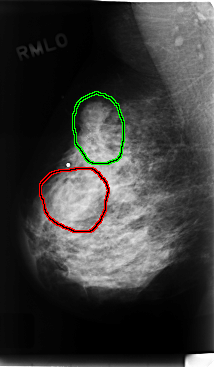

C_0223_1.RIGHT_MLO

FILE: C_0223_1.RIGHT_MLO.OVERLAY

TOTAL_ABNORMALITIES 2

ABNORMALITY 1

LESION_TYPE MASS SHAPE OVAL MARGINS CIRCUMSCRIBED

ASSESSMENT 3

SUBTLETY 5

PATHOLOGY BENIGN

TOTAL_OUTLINES 1

BOUNDARY

ABNORMALITY 2

LESION_TYPE CALCIFICATION TYPE PLEOMORPHIC DISTRIBUTION CLUSTERED

LESION_TYPE MASS SHAPE OVAL MARGINS ILL_DEFINED

ASSESSMENT 5

PATHOLOGY MALIGNANT